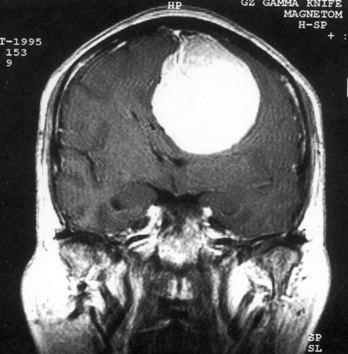

问题 病历摘要:??患者,男,40岁。发作性左下肢抽搐1年余,每次发作3~5分,每周发作1~2次。每次发作后感左下肢乏力,约半日后可自行恢复。既往身体健康。体检:神清,头顶部偏右有局限性骨性隆起(1.5×1.5cm),左鼻唇沟稍浅,伸舌居中。感觉、运动无明显异常。左浅反射减退,左下肢腱反射稍亢进,左Babinski征(-)。 术中下列哪些处理是错误的?提示:脑血管造影示上矢状窦中段闭塞,肿瘤有右脑膜中动脉和大脑前动脉分支供血。

选项 A.切皮前半小时给予抗生素 B.右顶开颅,切口至中线 C.电灼上矢状窦表面出血 D.对横跨在肿瘤表面的中央静脉电凝后切断 E.沿肿瘤和脑组织分界面以食指分离 F.连同肿瘤一起切除相连的矢状窦 G.切除受侵犯的硬膜,以人工脑膜修补 H.去除受侵犯的颅骨,以人工颅骨修补 I.术中静滴德巴金

答案 DE